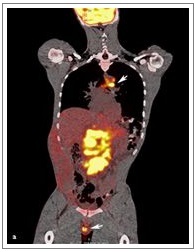

Primary Effusion Lymphoma with Extracavitary Presentation and A T-Cell Immunophenotype: A Potential Diagnostic Pitfall

Adam Stelling*, Hongying Tina Tan, Martina Zalom, Sheeja T Pullarkat

International Journal of Clinical Pathology and Diagnosis